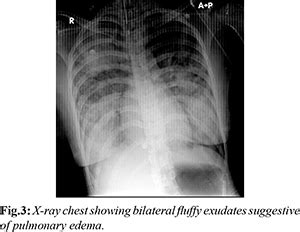

Neurogenic Pulmonary Edema : A Rare Presentation of Traumatic Brain Injury

casereports.in

AIIMS Doctors report Rare Case of Neurogenic Pulmonary Edema after High ...

speciality.medicaldialogues.in